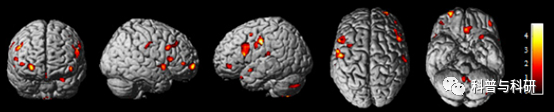

戴博士,博士后,特聘教授。中国老年医学学会认知障碍分会委员。担任SCI期刊《Journal of Thoracic Disease》杂志的助理编辑;SCI期刊《Frontiers in Neurology》、《Frontiers in Psychiatry》和 《BioMed Research International》杂志的客座编辑。担任《中国普通外科杂志》、《中国胸心血管外科临床杂志》及《临床与病理杂志》等期刊编委。已发表学术论文40余篇,Google scholar被引用700余次,h指数为13。主持国家自然科学基金等课题6项,参加省级以上课题13项。申请国家发明专利2项、软件著作权1个。参与编写专著2本。

林博士,博士后。浙江大学数学与应用数学学士,中国科学院大学神经生物学博士,芬兰赫尔辛基大学神经影像博士后。以第一作者在Human brain mapping等杂志发表机器学习等方面SCI文章8篇。熟悉影像学的各种主要数据分析方法,特别是基于机器学习的脑连接组学和影像组学。

许博士,多个功能神经影像学软件包开发者,主持国家自然科学基金等项目多个,发表学术论文30余篇,申请软件著作权多个。精通代码及神经影像学数据处理。

钟博士,PANDA软件开发者,发表SCI论文多篇,主持参加国自然多项。

田博士,神经影像学及心理学学科背景,精通Matlab、Python及R语言。。以第一作者发表SCI论文多篇,在功能磁共振和结构磁共振影像处理方面有丰富的经验。

梅老师,以第一作者发表SCI论文多篇,精通功能影像学数据方法处理,有多年培训经验,在功能磁共振数据处理方面具有极其丰富的经验。